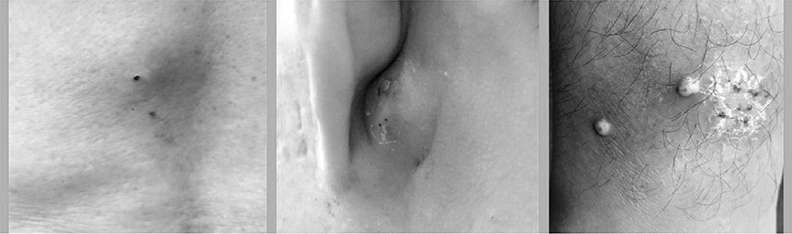

(提醒:以下有患部黑白照片)

粉瘤是良性囊腫易復發

疔瘡是可以痊癒的毛囊感染